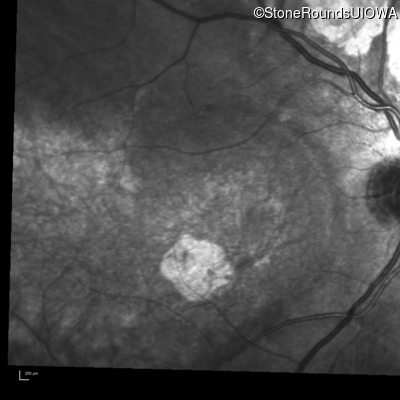

Infrared Fundus Photograph - Left - 20/125

Exemplar